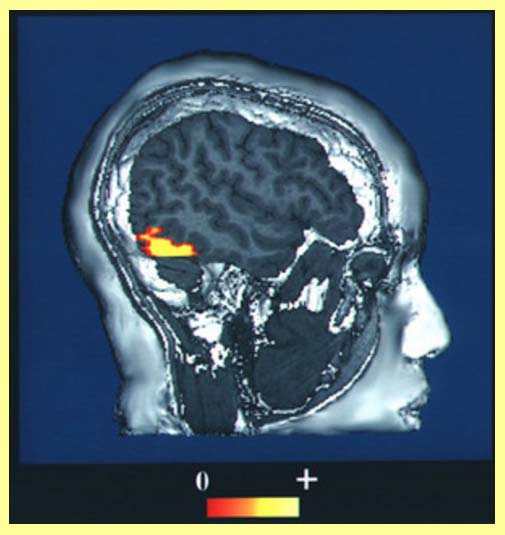

Mozek zobrazený funkční magnetickou rezonancí

Mozek zobrazený funkční magnetickou rezonancí

Naštěstí není ani možné takováto "odposlouchávání" mozku dělat nenápadně. Pittsburghští výzkumníci používají pro sledování mozku metodu zvanou zobrazení funkční magnetickou rezonancí.

Postup se v medicíně používá pro zjišťování chorobných změn v lidském organismu. Při sledování mozku zjišťuje, která jeho část právě pracuje. Pozná to podle toho, že potřebuje více krve, jež do ní přináší kyslík.